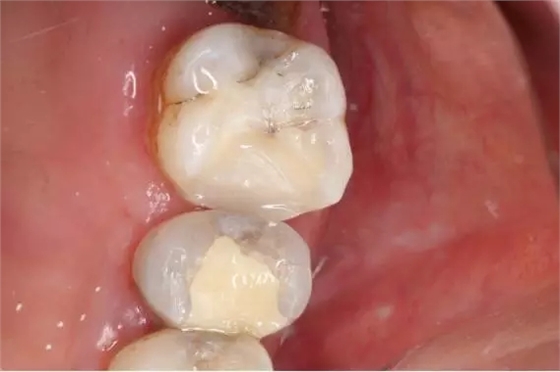

3.墊底和洞形修整

13.上橡皮障戴牙